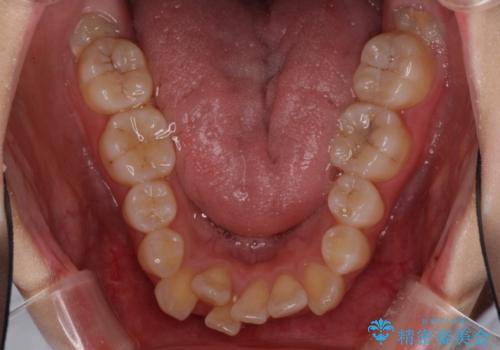

- 八重歯を気にして来院された患者様です。

上下ともに前突感と叢生が認められ、上顎の正中が著しく右側にずれていたため、上下左右第一小臼歯4本を抜歯し、ワイヤー矯正にて治療を行うこととしました。